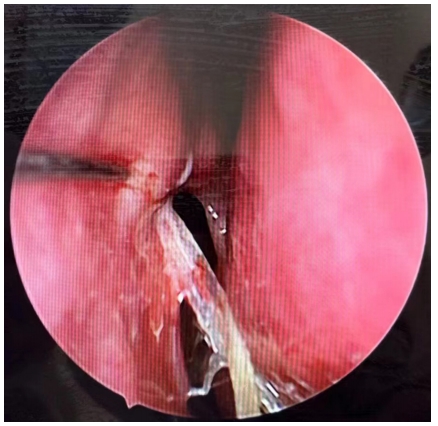

手术方法:术中沿中鼻甲前缘附着点上方约8 mm处做弧形切口,形成一约1 cm × 1.2 cm黏膜瓣,钝性分离至泪颌缝,以泪颌缝为标志,用美敦力(Medtronic,美国)IPC刨削动力系统粗磨,咬除上颌骨颈突,造一直径为1 cm大小的骨孔,暴露泪囊,经上泪小点置入探针,撑起泪囊壁,近上缘弧形切开泪囊内侧壁,形成一黏膜瓣,开放前组筛窦,剪开鼻黏膜瓣,使其贴附于泪囊造口周边骨面上,泪囊瓣与鼻黏膜瓣之间无需缝合,周围填充沾有妥布霉素地塞米松眼膏眼药膏的吸收性明胶海绵[14],见瘘口形成良好,检查无出血。合并泪总管、泪小管狭窄时植入泪道引流管,分别自上下泪小点插入引流管,自鼻腔内勾出并打结。术中同期处理鼻腔、鼻窦病变。手术均由同一位经验丰富技术熟练的医师完成。术后随访及处理:术后1个月内用药为布地奈德鼻喷雾剂2次/天,0.1%氟米龙滴眼液滴术眼3次/天。术后每2周复查1次鼻内镜检查,复查3次后根据恢复情况确定随访间隔时间,所有患者随访时间均大于6个月。随访内容包括以下3项:1)鼻内镜下鼻腔处理,清除鼻腔内血痂、分泌物、黏膜粘连及增生的肉芽组织,如发现肉芽组织增生(图1、3),则用枪镊夹除肉芽组织,造瘘口周围涂妥布霉素地塞米松眼膏,其中物理清除联合TA组予鼻黏膜下注射TA注射液(40 mg/mL)0.3 ~ 0.5 mL,保证注射面积覆盖80%肉芽组织创面(图2、4),间隔2周复查,如发现肉芽复发则再次清除并注射TA。2)泪道冲洗,分别经上下泪小点以地塞米松注射液和生理盐水冲洗泪道。3)如术中联合植入泪道引流管,一般于3个月后拔除。

图1 造瘘口肉芽组织增生

Figure 1 Granuloma formation in the ostium